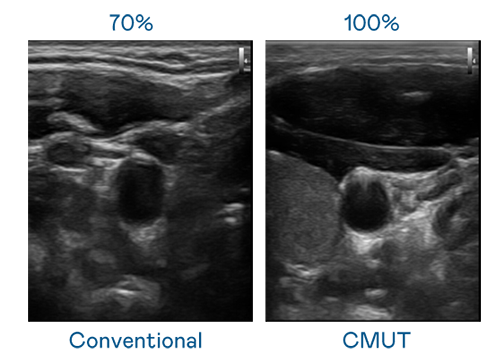

CMUT 技术是一种用电容式微机电元件来产生超音波讯号的技术。与传统 PZT 压电式技术相比,CMUT 频宽增加 30%,更宽频的超音波讯号让影像解析度大幅提升,是实现高影像品质医疗超音波扫描、促进精准医疗发展的关键技术。

大频宽带来超清晰影像

超音波影像的解析度高低,首先取决于探头能发出的讯号频宽。天美mv免费mv CMUT 可提供高清晰的超音波讯号,提供高频宽、高灵敏度、影像纹理细节更高的超音波影像,协助医护人员缩短影像判读时间及利用精准的医疗影像进行诊断。